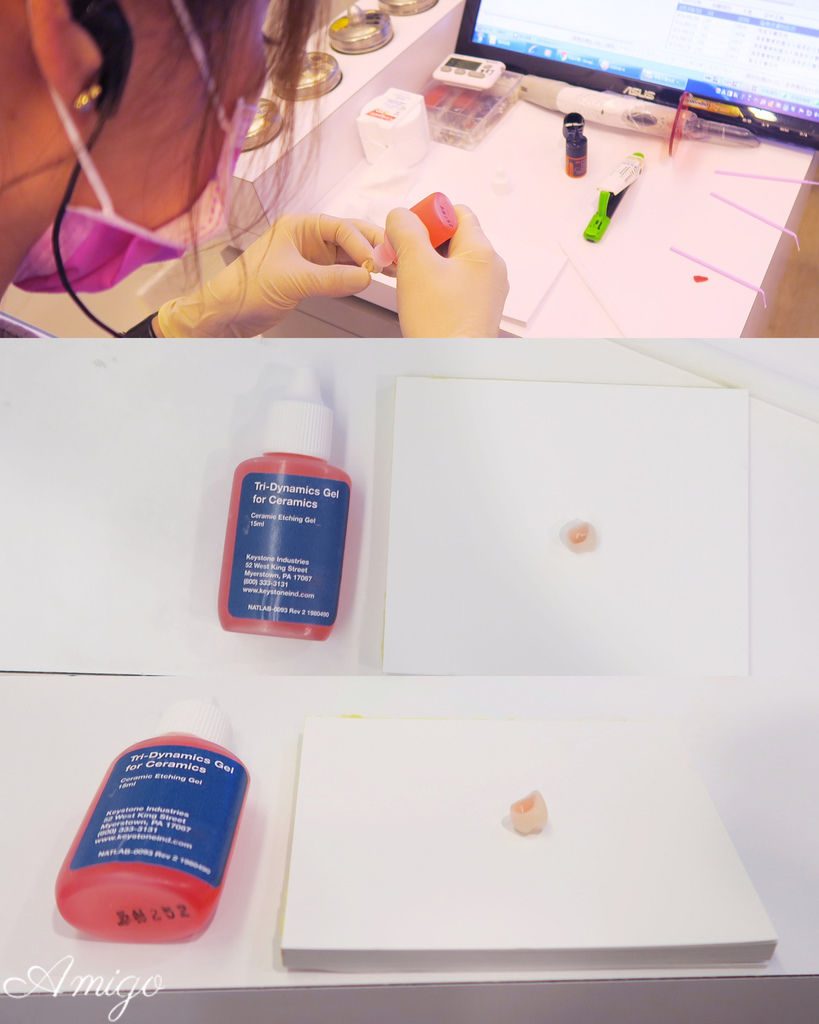

後續技師將假牙拿到技工室裡上色加工

完成後便交給醫師

以氫氟酸將全瓷假牙內部進行消毒

之後再沖洗乾淨▼▼▼